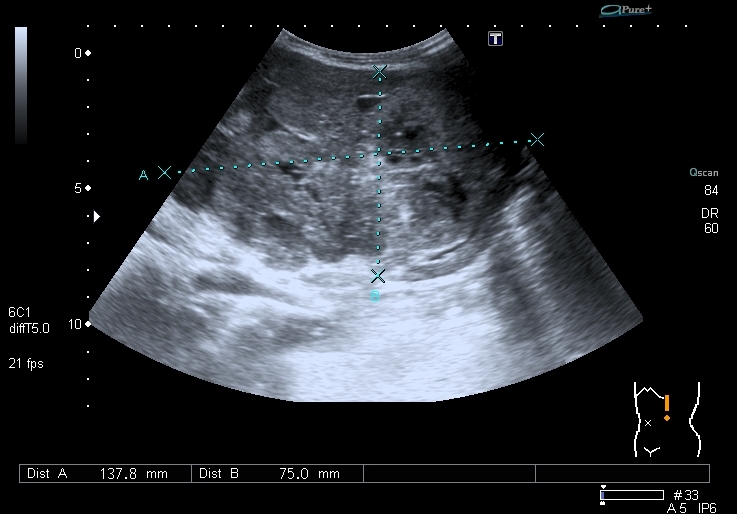

Предлагаю интересные изображения, полученные при сканировании лёгких через межрёберные промежутки и печень у ребёнка 4-х лет с подозрением на пневмонию

участок безвоздушной легочной ткани....похож на печень...пневмония в стадии опеченения...

Согласен в отношении нижней доли правого лёгкого, изменения в ней похожи на сливную инфильтрацию при пневмонии, хотя носят несколько многоузловой характер. Но то что мы видим со спины в левом лёгком на пневмоническую инфильтрацию не похоже.

Добавляю сканы печени, я думаю они являются хорошей подсказкой о природе изменений в лёгких